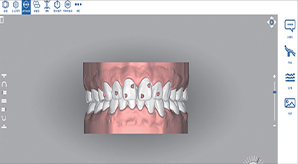

가상 3D 시뮬레이션 기술 활용

걸포탑치과의 치아교정은 얼굴모습, 치아위치, 턱 모양을

입체적으로 구현 및 분석하여 교정 후 모습을 미리 확인할 수 있는 체계적인 진단 시스템으로 진행됩니다.

교정 후 나의 모습을 미리 만나보세요!